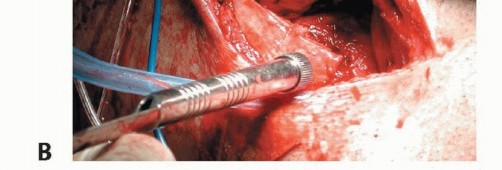

Using the standard medial approach, the distal end of the MCL often can be identified (TECH FIG 5A).

This attachment can be used in the reconstruction if the length is adequate; if not, it can be sutured to the reconstruction.

The allograft is then fixed femorally (as described earlier) and routed along the course of the superficial MCL (TECH FIG 5B).

The posterior and anterior portions of the superficial MCL can then be individually attached to the tibia.

- TECH FIG 5 • A. Medial incision. The chronically disrupted MCL stump can be visualized through the sartorius fascia. B. An Achilles tendon allograft has been sized to fit in a bone trough at the epicondylar origin of the MCL (depth gauge shown in preparation for screw fixation of the bone block). The allograft has been routed along the course of the MCL and fans out to provide the posterior and anterior portion of the MCL. (Courtesy of Mark D. Miller, MD.)